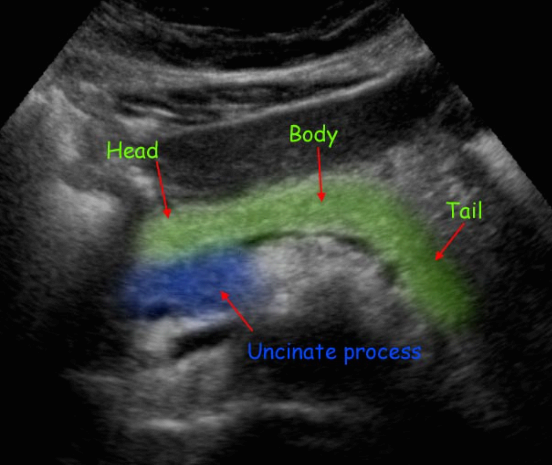

췌장의 해부학 (normal anatomy)

췌장은 복막 후 장기(retroperitoneal organ)로 다양한 효소를 생산하여 음식물을 소화시킨다. 췌장은 췌두부(pancreas head), 췌체부(body), 췌미부(tail)로 구분하며 췌두부에는 구상돌기(uncinate process)가 있다. 태생기에 복측(ventral pancreas)과 배 측(dorsal pancreas)으로 발생하여 췌체부는 전측(anterior)으로 췌두부와 췌미부는 후측으로 휘어져 있다.

췌장의 크기는 길이 약 12cm이고 두께는 췌두부의 약 2.5cm, 체체부 약 2cm, 췌미부 1.5~2cm, 무게는 80g 정도이다.

췌장은 우측에 십이지장, 좌측에 비장, 전측에 위장, 상측에 간, 후측에 대동맥, 대정맥, 상장간막정맥, 상장간막동맥, 비장정맥이 있다.

정상췌장의 초음파적 소견

췌장은 막이 없는 장기로 초음파상 경계면이 확실하지 않다. 췌장의 에코는 간보다 약간 밝거나 같으며 균질하다. 나이가 증가하면서 위축되고 지방침착으로 인해 췌장 실질이 밝아진다. 주췌관의 직경은 3mm 이상이면 확장으로 보나 분단위로 수축과 확장을 반복하여 변하기 때문에 시간에 따라 확인해야 한다. 실제검사에서 대칭성의 소실, 외곽선의 급격한 변화, 에코변화등을 주의 깊게 관찰해야 한다.

- 돌출 없는 매끈한 모양의 실질, 두께 4cm 이하

- 간실질보다 조금 높은 균질한 에코

- 균일한 직경의 2mm 미만 췌관

- 예리한 모양의 구상돌기

- 주위정맥들의 눌림이 없다

- 췌장주위 비정상 액체저류가 없다

- 길이 12cm

- 두께 head 2.5cm (2.5cm 이상이면 종대), body 2cm (2cm 이상이면 종대), tail 1.5~2cm (2cm 이상이면 종대)